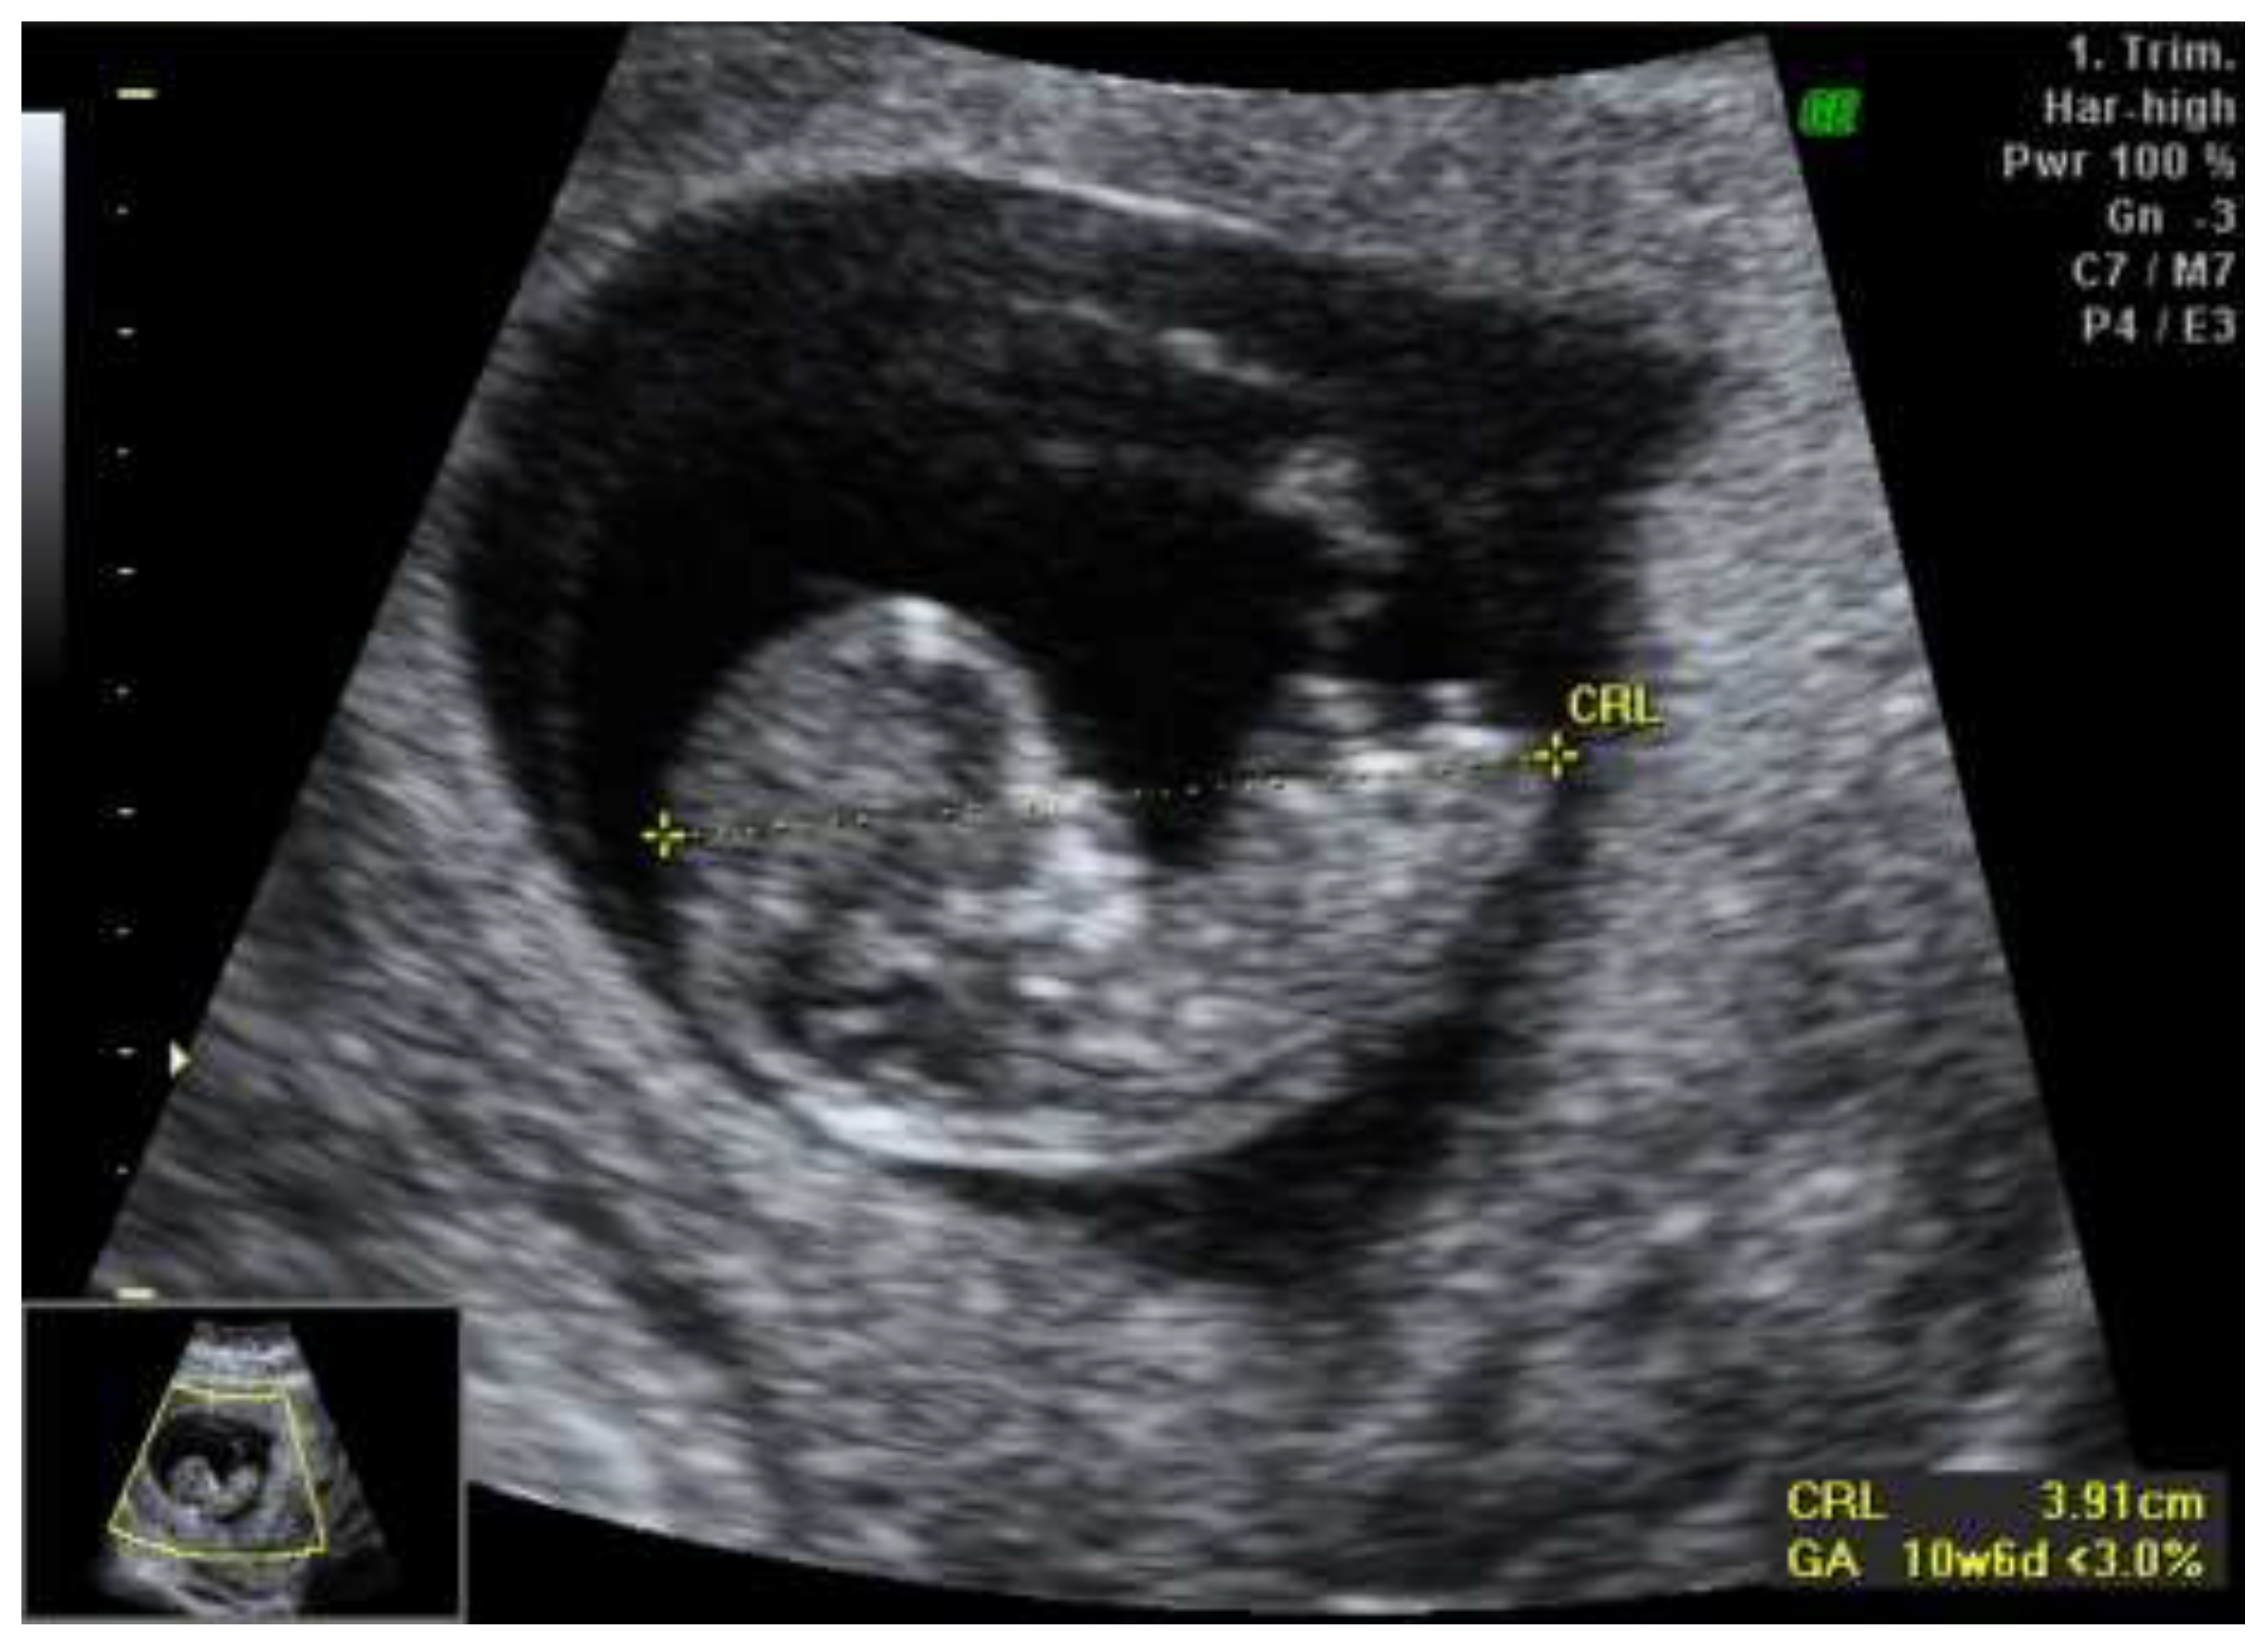

We report a case of a 28-year-old primigravida who presented for routine prenatal care at 11 weeks of gestation. Initial ultrasound examination revealed asymmetric growth restriction, raising suspicion for potential fetal anomalies. The anatomy appeared normal, with no overt structural defects noted. The first-trimester combined screening test for chromosomal anomalies indicated a low risk, with a PAPP-A of 0.7 MoM and a beta-hCG of 0.73 MoM, suggesting a favorable outcome regarding common aneuploidies (Figure 1).

Figure 1. First trimester scan revealing asymetric fetal growth restriction.